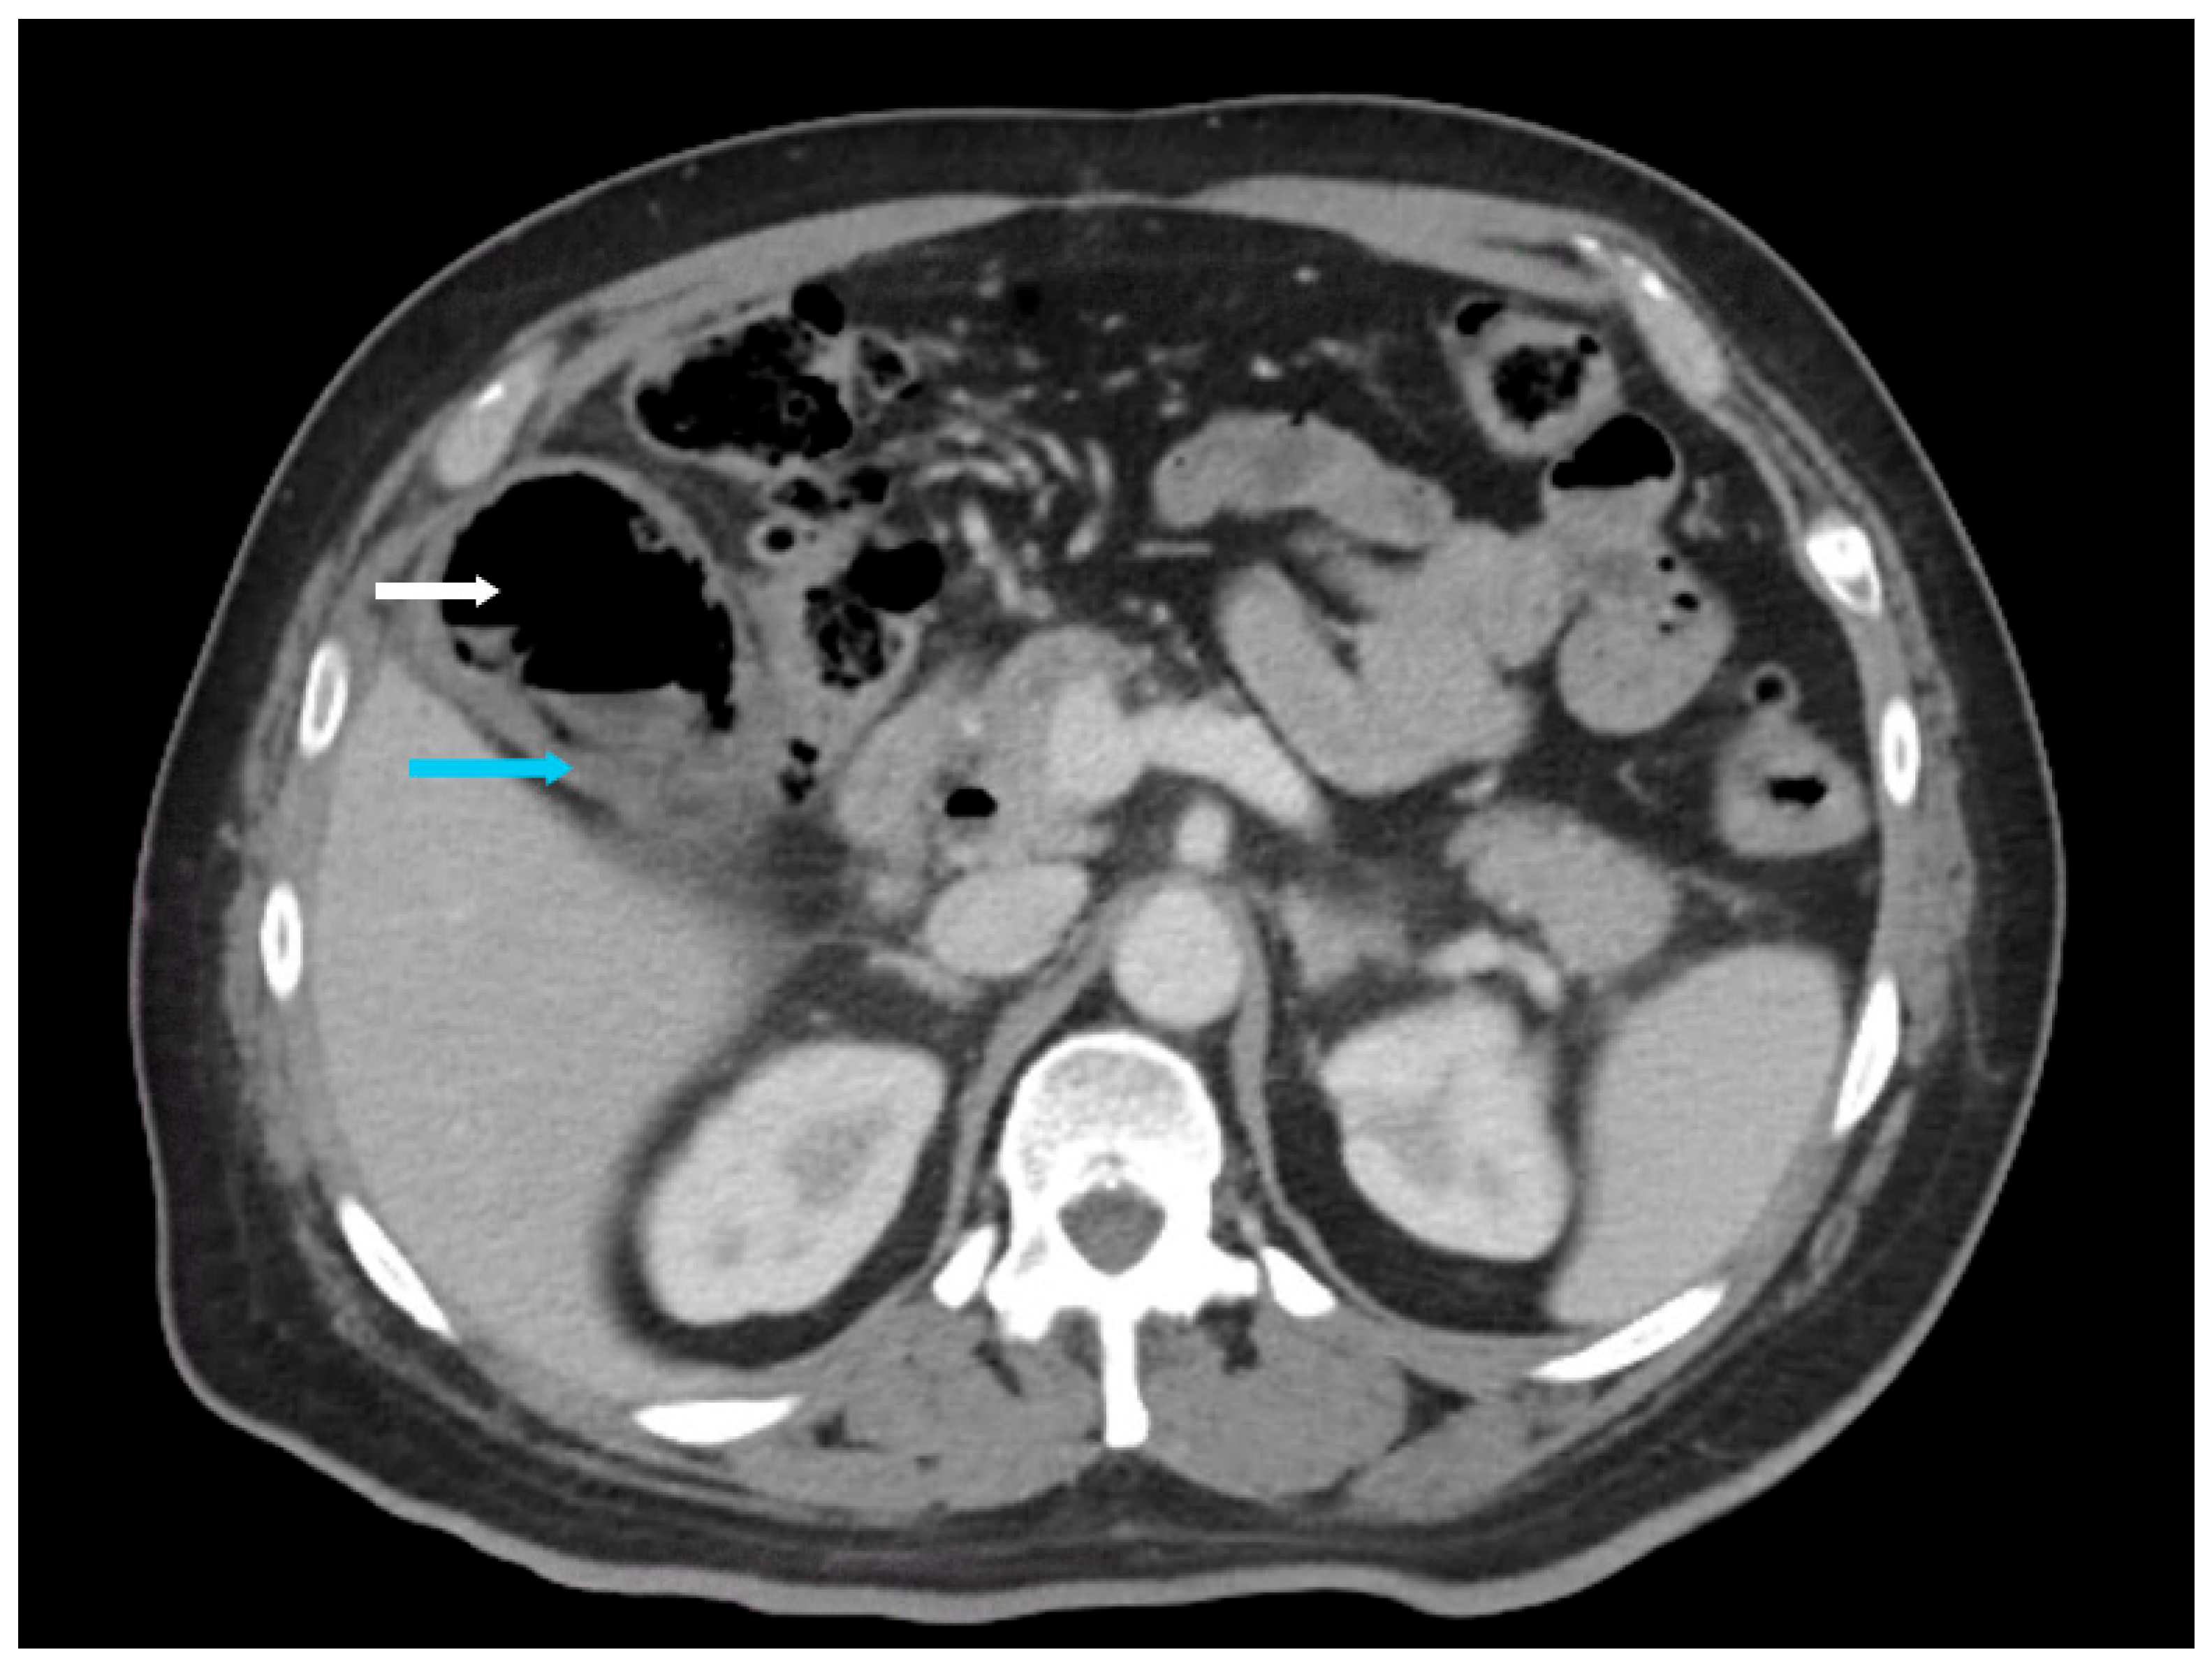

The hallmark CT findings of EC include the presence of gas within the gallbladder wall, lumen, or pericholecystic tissues. Gas may appear as curvilinear, punctate, or mottled foci along the gallbladder wall, as seen in Figure 3, Figure 4 and Figure 5. Intraluminal gas can create air-fluid levels or completely fill the gallbladder, while gas in adjacent tissues may signify transmural necrosis or perforation [7]. CT can also identify complications such as pericholecystic abscess, emphysematous spread to adjacent organs (e.g., liver or duodenum), or intraperitoneal free air in the case of perforation and rupture [18].

In addition to identifying gas, contrast-enhanced CT allows for detailed assessment of gallbladder wall thickening, stratification, edema, and vascular compromise, which may suggest progression to gangrenous cholecystitis [19]. CT is particularly effective in detecting subtle or early emphysematous changes. Moreover, noncontrast CT may be sufficient for diagnosis in some cases, as gas is readily visible without intravenous contrast. However, contrast-enhanced CT can provide additional information regarding gallbladder perfusion and the presence of adjacent inflammation or abscess formation, which may influence management decisions.

Figure 5. Axial contrast-enhanced computed tomography abdomen in the arterial phase (slice thickness 3 mm; soft tissue window, WW 350, WL 40) of a 39-year-old male diabetic patient with emphysematous cholecystitis presenting with abdominal pain. Extensive air in the gallbladder lumen (white arrow) and gallbladder wall edema (blue arrow) were incidentally noted.